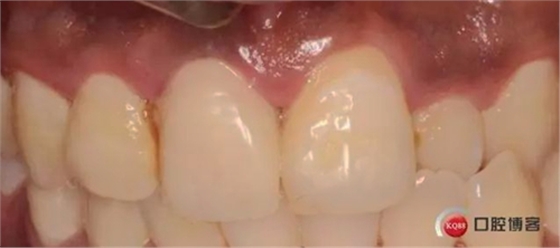

兩月后牙齦恢復(fù)正常穩(wěn)定。正式取模,E.max鑄瓷修復(fù)

可以看出牙齦袖口很漂亮,修復(fù)體外形也不錯(cuò),就是顏色偏白一點(diǎn),讓患者改色,患者覺得已經(jīng)很滿意了,而且考慮其他牙以后做美白,所以不換了。

可以看出修復(fù)體的邊緣密合度都很好。希望這次修復(fù)能夠讓這顆牙多服役幾年吧